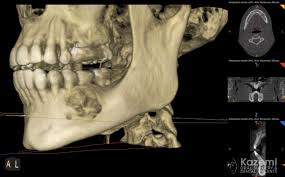

Difficulties In The Diagnosis Of Periapical Translucencies And In The Classification Of Cemento Osseous Dysplasia Bmc Oral Health Full Text

Difficulties In The Diagnosis Of Periapical Translucencies And In The Classification Of Cemento Osseous Dysplasia Bmc Oral Health Full Text from media.springernature.com